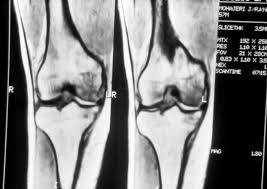

Medial Femoral Condyle, Spect Ct Delineation Of Patellar And Femorotibial Overload After Knee Arthroplasty - Please see our knee injury protocol for additional information on this topic.. An articular cartilage injury, or chondral injury, may occur as a result of a pivot or twist on a bent knee, similar to the motion that can cause a meniscus tear. Osteonecrosis of the medial femoral condyle presents as a sudden onset of pain on the medial side of the knee. Osteonecrosis of the medial femoral condyle can be treated in a variety of ways depending on the stage of the disease. The femoral condyle allograft has been used for resurfacing cartilage defects with mature hyaline cartilage for several decades, with very high success rates. Your knee mri will often show a:

They are called the medial and the lateral femoral condyle, respectively. An imbalance of the muscles around the knee (some muscles are weaker than others.) overuse (repeated bending or twisting) of the knee joint, especially during sports. However, two of the patients had one or more fractures missed when they first presented. The medial femoral condyles are the bony protrusions on the inside edge of the bottom of the femur bone in each thigh. Osteochondritis dissecans (ocd) is an acquired, reversible, idiopathic lesion. Osteonecrosis of the medial femoral condyle presents as a sudden onset of pain on the medial side of the knee. This is associated with a positive bone scan and, frequently, a radiolucent lesion in the subchondral zone. Methods sixteen knees with a small medial femoral. The medial condyle is larger than the lateral (outer) condyle due to more weight bearing caused by the centre of mass being medial to the knee. Medial condyle of femur from wikipedia, the free encyclopedia the medial condyle is one of the two projections on the lower extremity of femur, the other being the lateral condyle. Root tear (radial tear) of the medial meniscus mild or moderate knee arthritis Osteonecrosis of the medial femoral condyle can be treated in a variety of ways depending on the stage of the disease. Of the six patients who had suffered an isolated fracture of their medial condyle, four of the patients had their fractures diagnosed on the first visit.

The radiographs demonstrated abnormal contour of the medial femoral condyle, consistent with an osteochondral defect, and a fabella posterior to the knee. Methods sixteen knees with a small medial femoral. It acts to support a significant amount of the patient's body weight. An imbalance of the muscles around the knee (some muscles are weaker than others.) overuse (repeated bending or twisting) of the knee joint, especially during sports. If there is a fracture (break) in part of the condyle, this is known as a fracture of the femoral condyle. The medial femoral condyle is supplied by a plexus of vessels from the descending genicular artery and the medial superior genicular artery. Damage may also be the result of a direct blow to the knee. Palpable to either side of the knee joint when it is bent, they are known specifically as the medial and lateral femoral condyles.

An articular cartilage injury, or chondral injury, may occur as a result of a pivot or twist on a bent knee, similar to the motion that can cause a meniscus tear. An imbalance of the muscles around the knee (some muscles are weaker than others.) overuse (repeated bending or twisting) of the knee joint, especially during sports. Juvenile ocd lesions have a better healing prognosis than adults. Osteonecrosis of the medial femoral condyle presents as a sudden onset of pain on the medial side of the knee. The radiographs demonstrated abnormal contour of the medial femoral condyle, consistent with an osteochondral defect, and a fabella posterior to the knee. Please see our knee injury protocol for additional information on this topic. Chondral injuries may accompany an injury to a ligament, such as the anterior cruciate ligament. Medial condyle of femur from wikipedia, the free encyclopedia the medial condyle is one of the two projections on the lower extremity of femur, the other being the lateral condyle. In the knee, chondromalacia is usually related to injury, overuse of the knee, and poorly aligned muscles and bones around the knee joint. The motions of the condyles include rocking, gliding and rotating. One presumed mechanism of injury is a stieda fracture (avulsion injury of the medial collateral ligament at the medial femoral condyle). Generally, ocd seems to affect males more commonly than females (between 2:1 and 3:1). According to the hospital for special surgery, the medial femoral condyle is the inside of the knee, and health issues dealing with it can be treated.